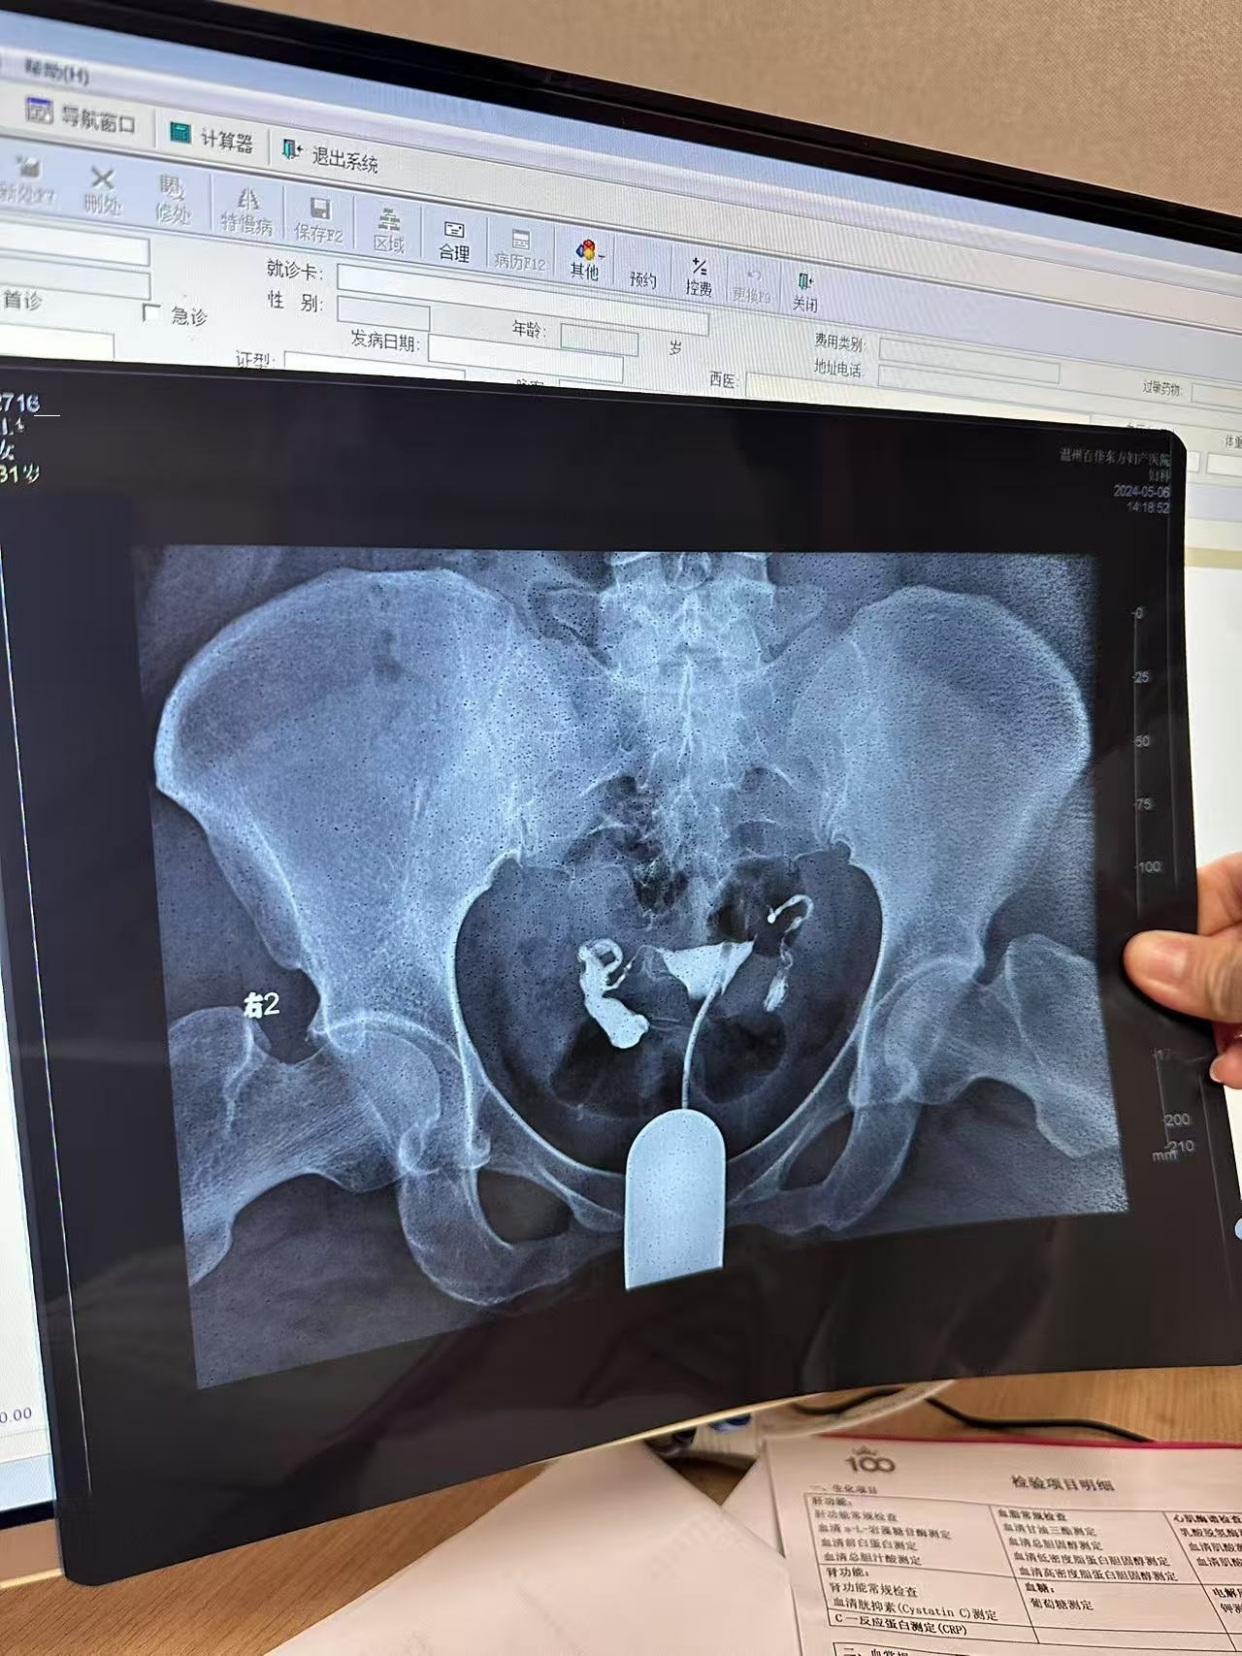

5、常规检查患者需要完成一系列常规检查,包括乙肝丙肝梅毒艾滋等传染病筛查同时进行凝血系列心电图检查,以及测量血压等,以确保患者符合造影检查的条件放置留置针在检查前,需要在患者的肘部放置留置针留置针用于后续注射造影剂,以便进行造影检查注射造影剂并检查通过留置针向患者体内注射;输卵管造影检查是通过将显影的造影剂注入宫腔,观察输卵管形态及盆腔情况的一种检查方法以下是输卵管造影检查的具体步骤术前准备在造影检查开始前,患者需拍摄一张盆腔的平片,以便后续对比观察消毒麻醉检查开始前30分钟进行消毒处理,以减少感染风险同时进行麻醉,通常选择局部麻醉,以减少输卵管的;冠状动脉造影是一种重要的诊断技术,用于检查冠心病这项检查能够帮助医生了解心脏血管的具体情况,从而制定合适的治疗方案进行冠状动脉造影检查的步骤主要包括以下几个方面首先,患者需要提前做好准备,包括禁食至少8小时,以确保检查过程顺利进行同时,医生会对患者进行全面的评估,包括血压心率等指标;导管插入时可能引发轻微疼痛或压迫感,但通常可耐受到达目标位置后,医生经导管注射造影剂,使冠状动脉显影通过X光机实时成像,医生可观察血管是否存在狭窄堵塞或动脉瘤等病变必要时,医生会同步进行血管压力测量支架植入等操作检查后护理患者需在恢复室观察30分钟至数小时,确认无过敏反应心律。